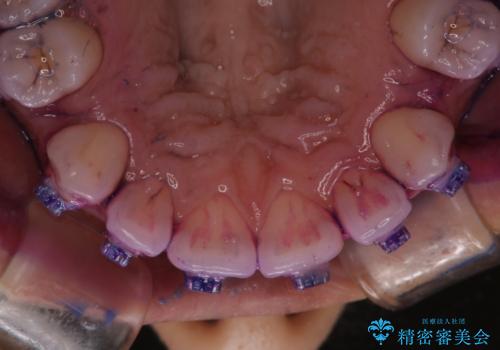

- 審美装置でのワイヤー矯正中の方です。月に1度の調整の際に一緒にクリーニンングもしてほしいとのことでした。

ワイヤーを上下外して、PMTC60分コースを行いました。

ワイヤー矯正中はブラッシングが難しくなるため、磨き残しが多くなることがあります。

また、矯正で歯の移動があると今までなかったところに隙間が出てきたり、ガタつきが解消されてきたりすることで、お口の中の環境が変わります。

矯正治療中も清潔な口腔内を保つことは、とても大切です。そのため、定期的に専門的な機械・材料を使用したProfessinnalcleaning(pmtc)を行うことがおススメです。